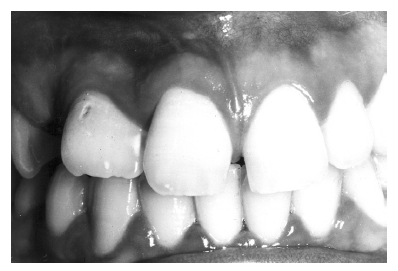

Figure 29 - Maxillary Right Lateral Incisor Macrodont

Figure 29